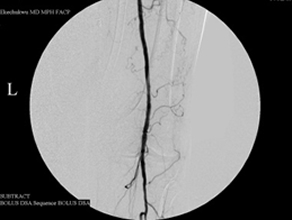

This 75-year-old man’s primary care doctor referred him to my clinic because of left leg cramps after ambulating a few blocks and I found that his left superficial femoral artery was occluded (left column images). Using catheters, wires, balloons, and a covered stent, I restored blood flow through the blocked artery and his problem resolved (right column images).